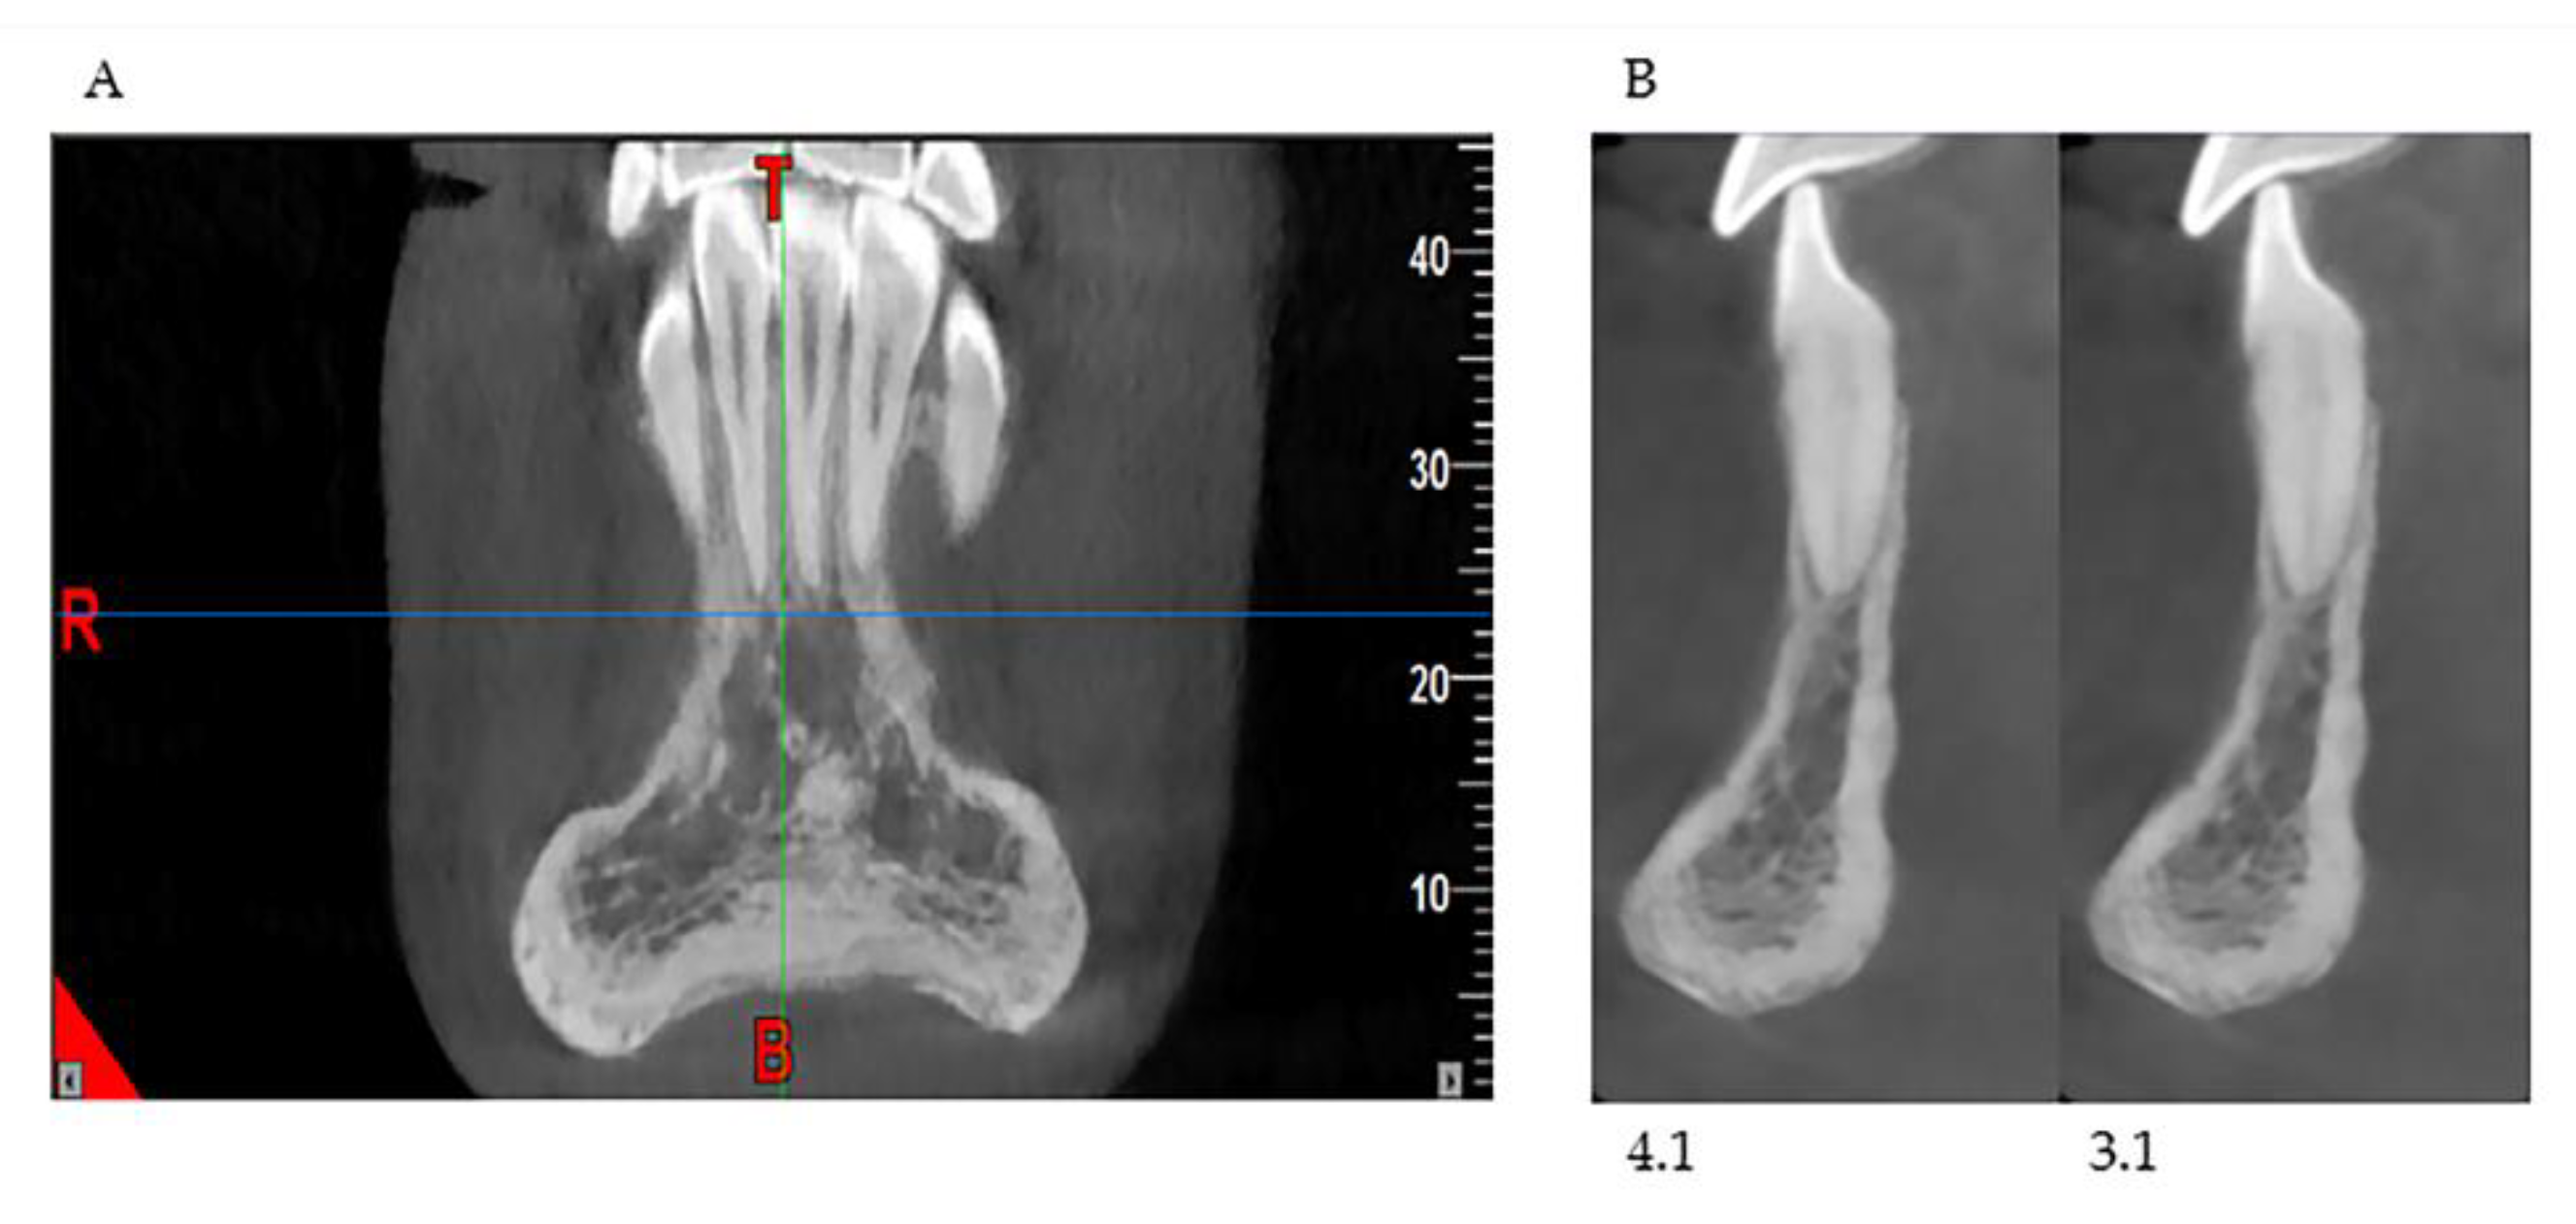

In our retrospective analysis, we identified the following parameters and adhered to strict reference planes for the measurement with CBCT. On the paraxial plane, elements 3.1 and 4.1 were identified, and measurements were made on these elements; in fact, from this line, the eminence of the chin guard symphysis (X) was evaluated orthogonally (90°) (Figure 2a). On the coronal plane, positioning between the two lower central incisors, the maximum point (C1), and the minimum point (C2) of the chin guard symphysis cortical on the horizontal plane were evaluated (Figure 2b).

Figure 2. Cone beam Computed Tomography (CBCT) measurements in the paraxial 4.1, 3.1. measurement X-plane (a) and coronal measurement C2 and C1 (b) plane.